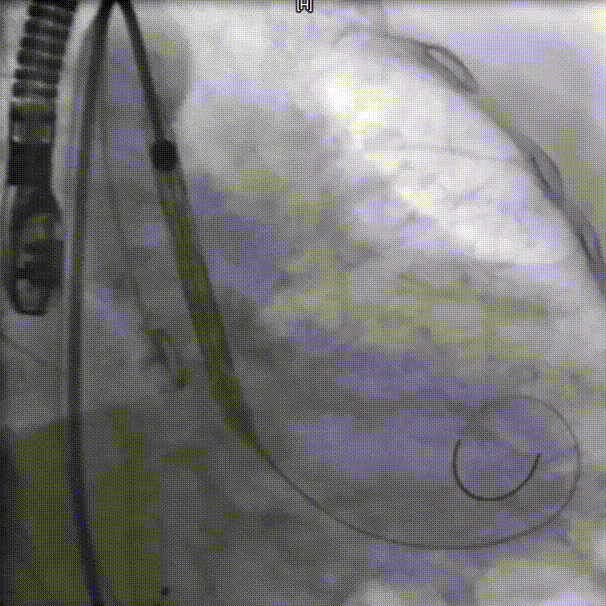

输送器过弓

瓣下3mm定位

左冠窦侧偏深,需回收再定位

回收调整至零位定位,释放到工作位位置合适

完全释放后无反流,冠脉灌注良好